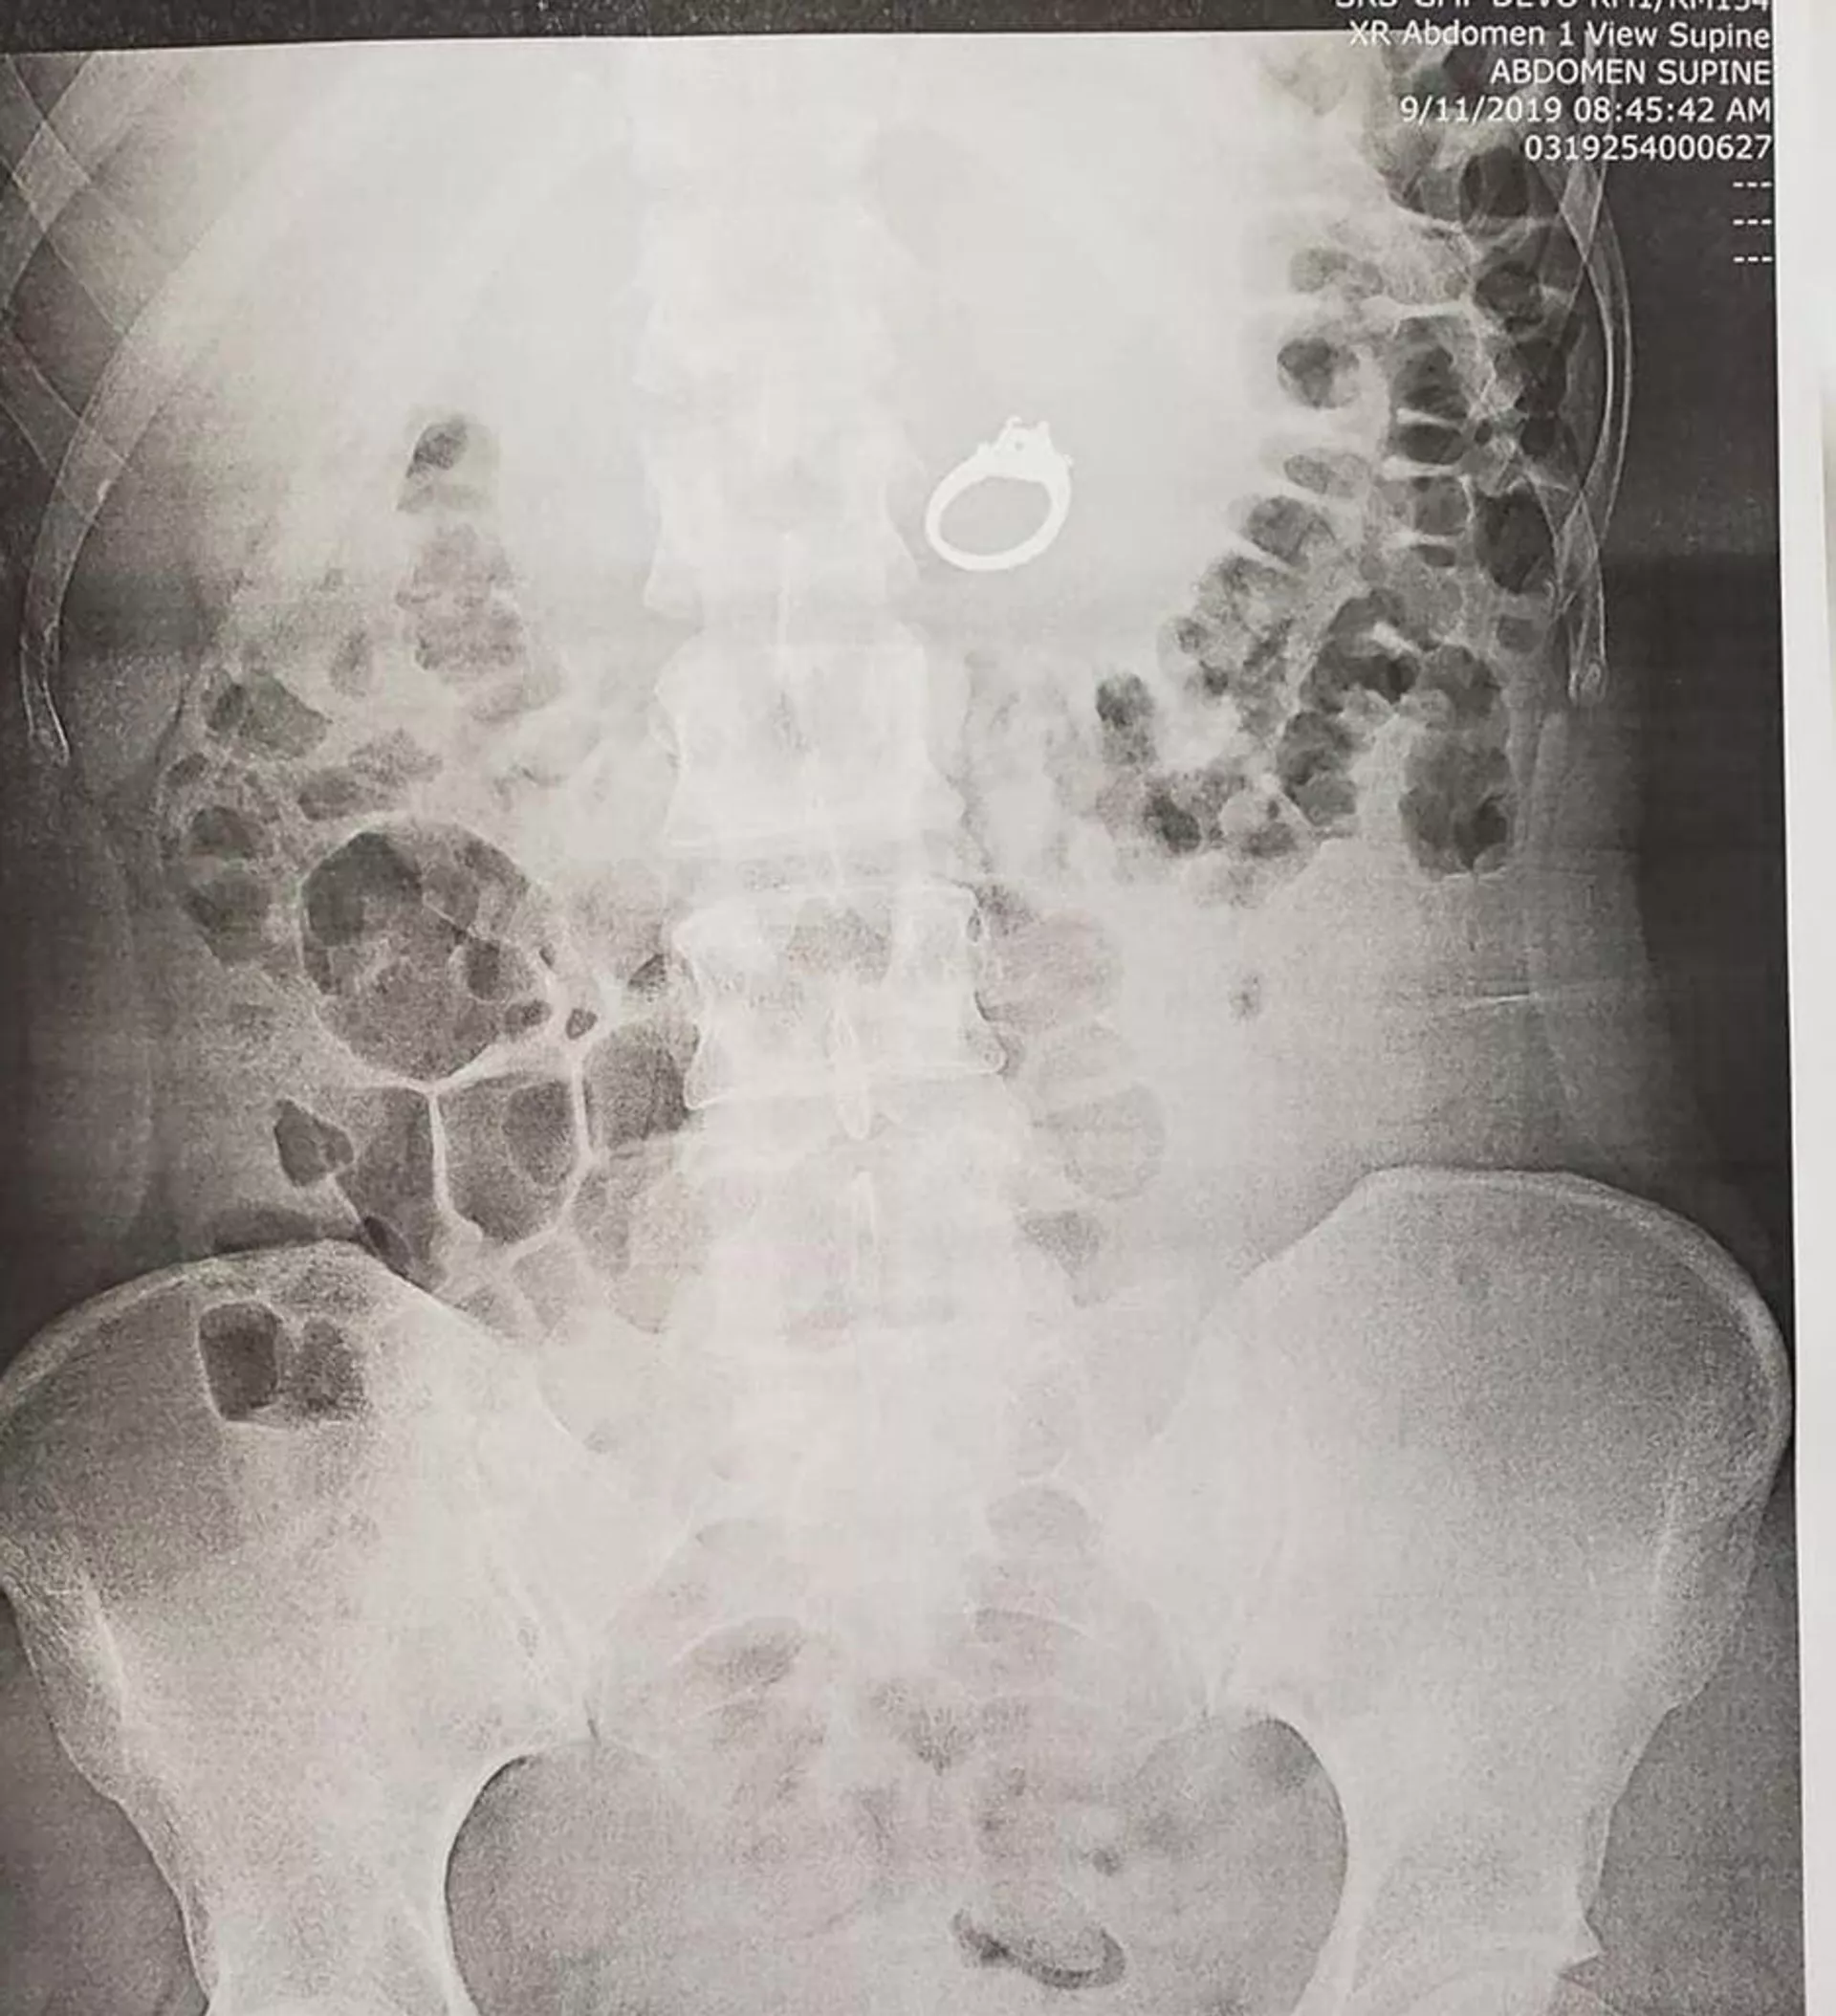

Phim chụp X-quang cho thấy chiếc nhẫn nằm trong dạ dày. Các bác sĩ không muốn mạo hiểm, khi chờ đợi cho món trang sức đi ra một cách tự nhiên và quyết định áp dụng phương pháp nội soi. Liệu trình điều trị đã diễn ra an toàn không có biến chứng, các bác sĩ đã lấy chiếc nhẫn ra khỏi bụng cô gái.